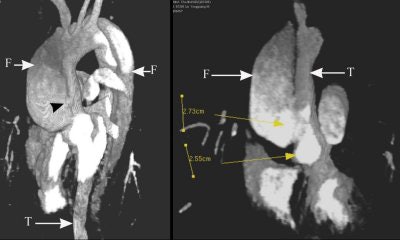

The series of images illustrate the typical manifestations of aortic dissection, including Stanford A (top image, both VR; second image, axial MPR) and Stanford B (third image, arterial phase VR, venous phase VR; fourth image, MIP and VR; fifth image, axial MPR). T = true lumen. F = false lumen. Black arrowhead = entry site. All images courtesy of Qi Liu, Ph.D.

The initial entry site of Stanford B and its relationship with left subclavian artery (top images, both VR).